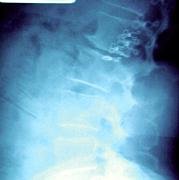

Radiographic weightbearing imaging studies were performed to evaluate the patient's lumbar spine and hips. There was marked reduction in disc height, retrospondylolisthesis of the first lumbar vertebra onto the second lumbar vertebra with reduction in size of foramen. There were proliferative osteophytes (overgrowth of bone forming hard bars) and moderate anterior traction spurring demonstrated. There was right laterolisthesis of the spinous processes accompanied by right concavity scoliosis. The acetabuli and hip joint spaces were well-maintained.

The ways that a foramen may be diminished in size are basically threefold: loss in disc height, subluxation of facets, and stenosis, or narrowing of the intervertebral foramen. In the presence of instability, the lax facet capsule allows the superior facet to move backward and forward with rotation. In this patient, the spinous process of L1 and L2 have been rotated; the superior facet moved anteriorly; the joint space had opened and the lateral canal was markedly narrowed. In the presence of fixations or advanced degenerative changes to stabilize the affected segment, little or no movement should take place at affected level. The lateral canal is fixed because of the degenerative deformity. Thus, two factors may be involved in producing the entrapment: subluxation of posterior facets, (superior facet moves superior and anterior), and enlargement of facet by osteophytic involvement that further narrows the lateral canal. The diagnostic imaging of choice is a CT scan.